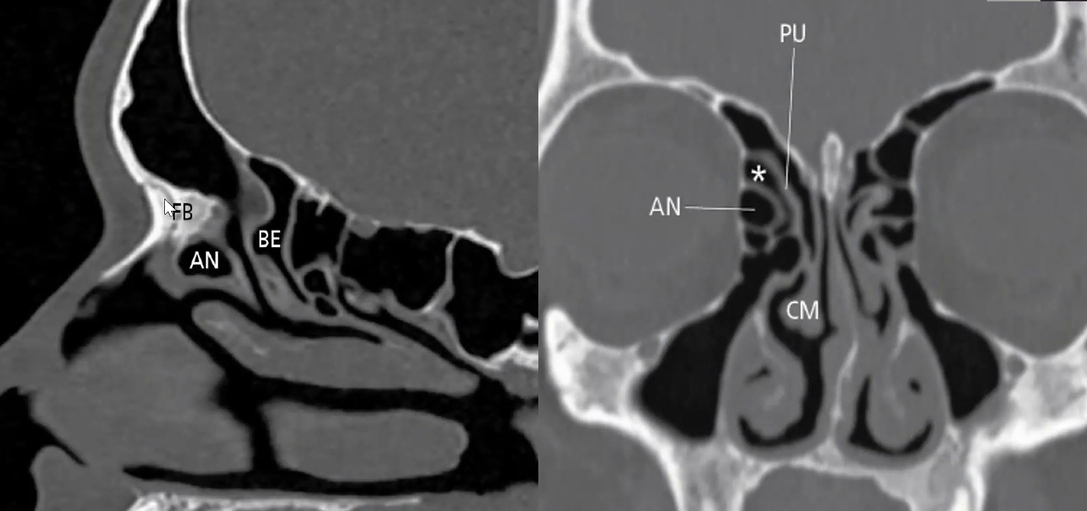

Cite o conceito de Agger Nasi e Bula Etmoidal.

• Agger Nasi: célula etmoidal mais anterior, situada na inserção anterior da concha média na parede lateral (forma a axila da concha média).

• Bula Etmoidal: maior célula etmoidal anterior (mas pode estar subdesenvolvida ou ausente em até 8% dos casos). Lateralmente tem a lâmina papirácea e posteriormente o recesso retrobular. Superiormente pode ter a fóvea etmoidal ou recesso suprabular.

É um fundo cego (asterisco na imagem) formado pela inserção do PU na lâmina papirácea (situação mais prevalente). A drenagem do frontal se dá no meato médio.